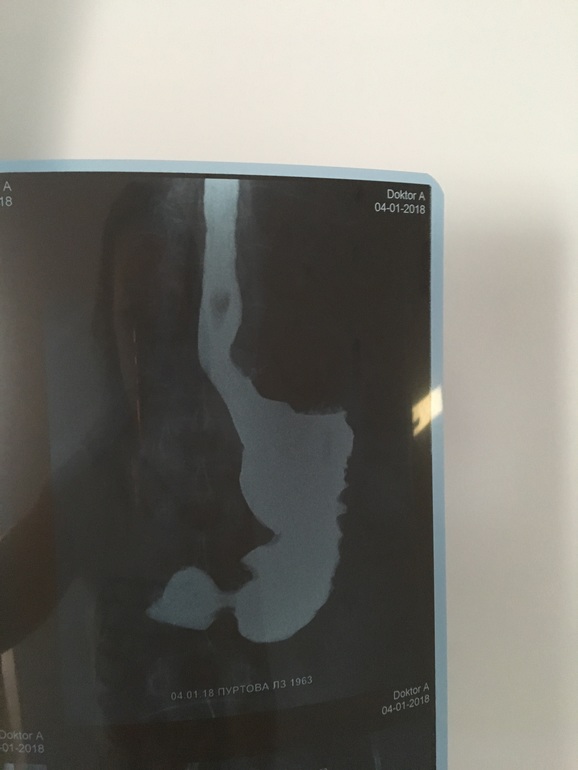

ГастроэнтерологияПомогите пож-та, может было у кого также. Беда произошла с мамой, резко ухудшилось состояние, в горле и груби как будто кол, отрыжка очень-очень часто. Сегодня сделали рентгенографию с барием, поставили диагноз недостаточность кардии, гастрит, дуоденит. У кого были такие диагнозы, что принимали? Нам назначенные таблетки пока никак не действуют. Назначили нольпаза,итопра,новобисмол. Ещё снимок мне не нравится, какая то тень на пищеводе, но врач сказал не страшно это. Может есть кто разбирается в снимках.